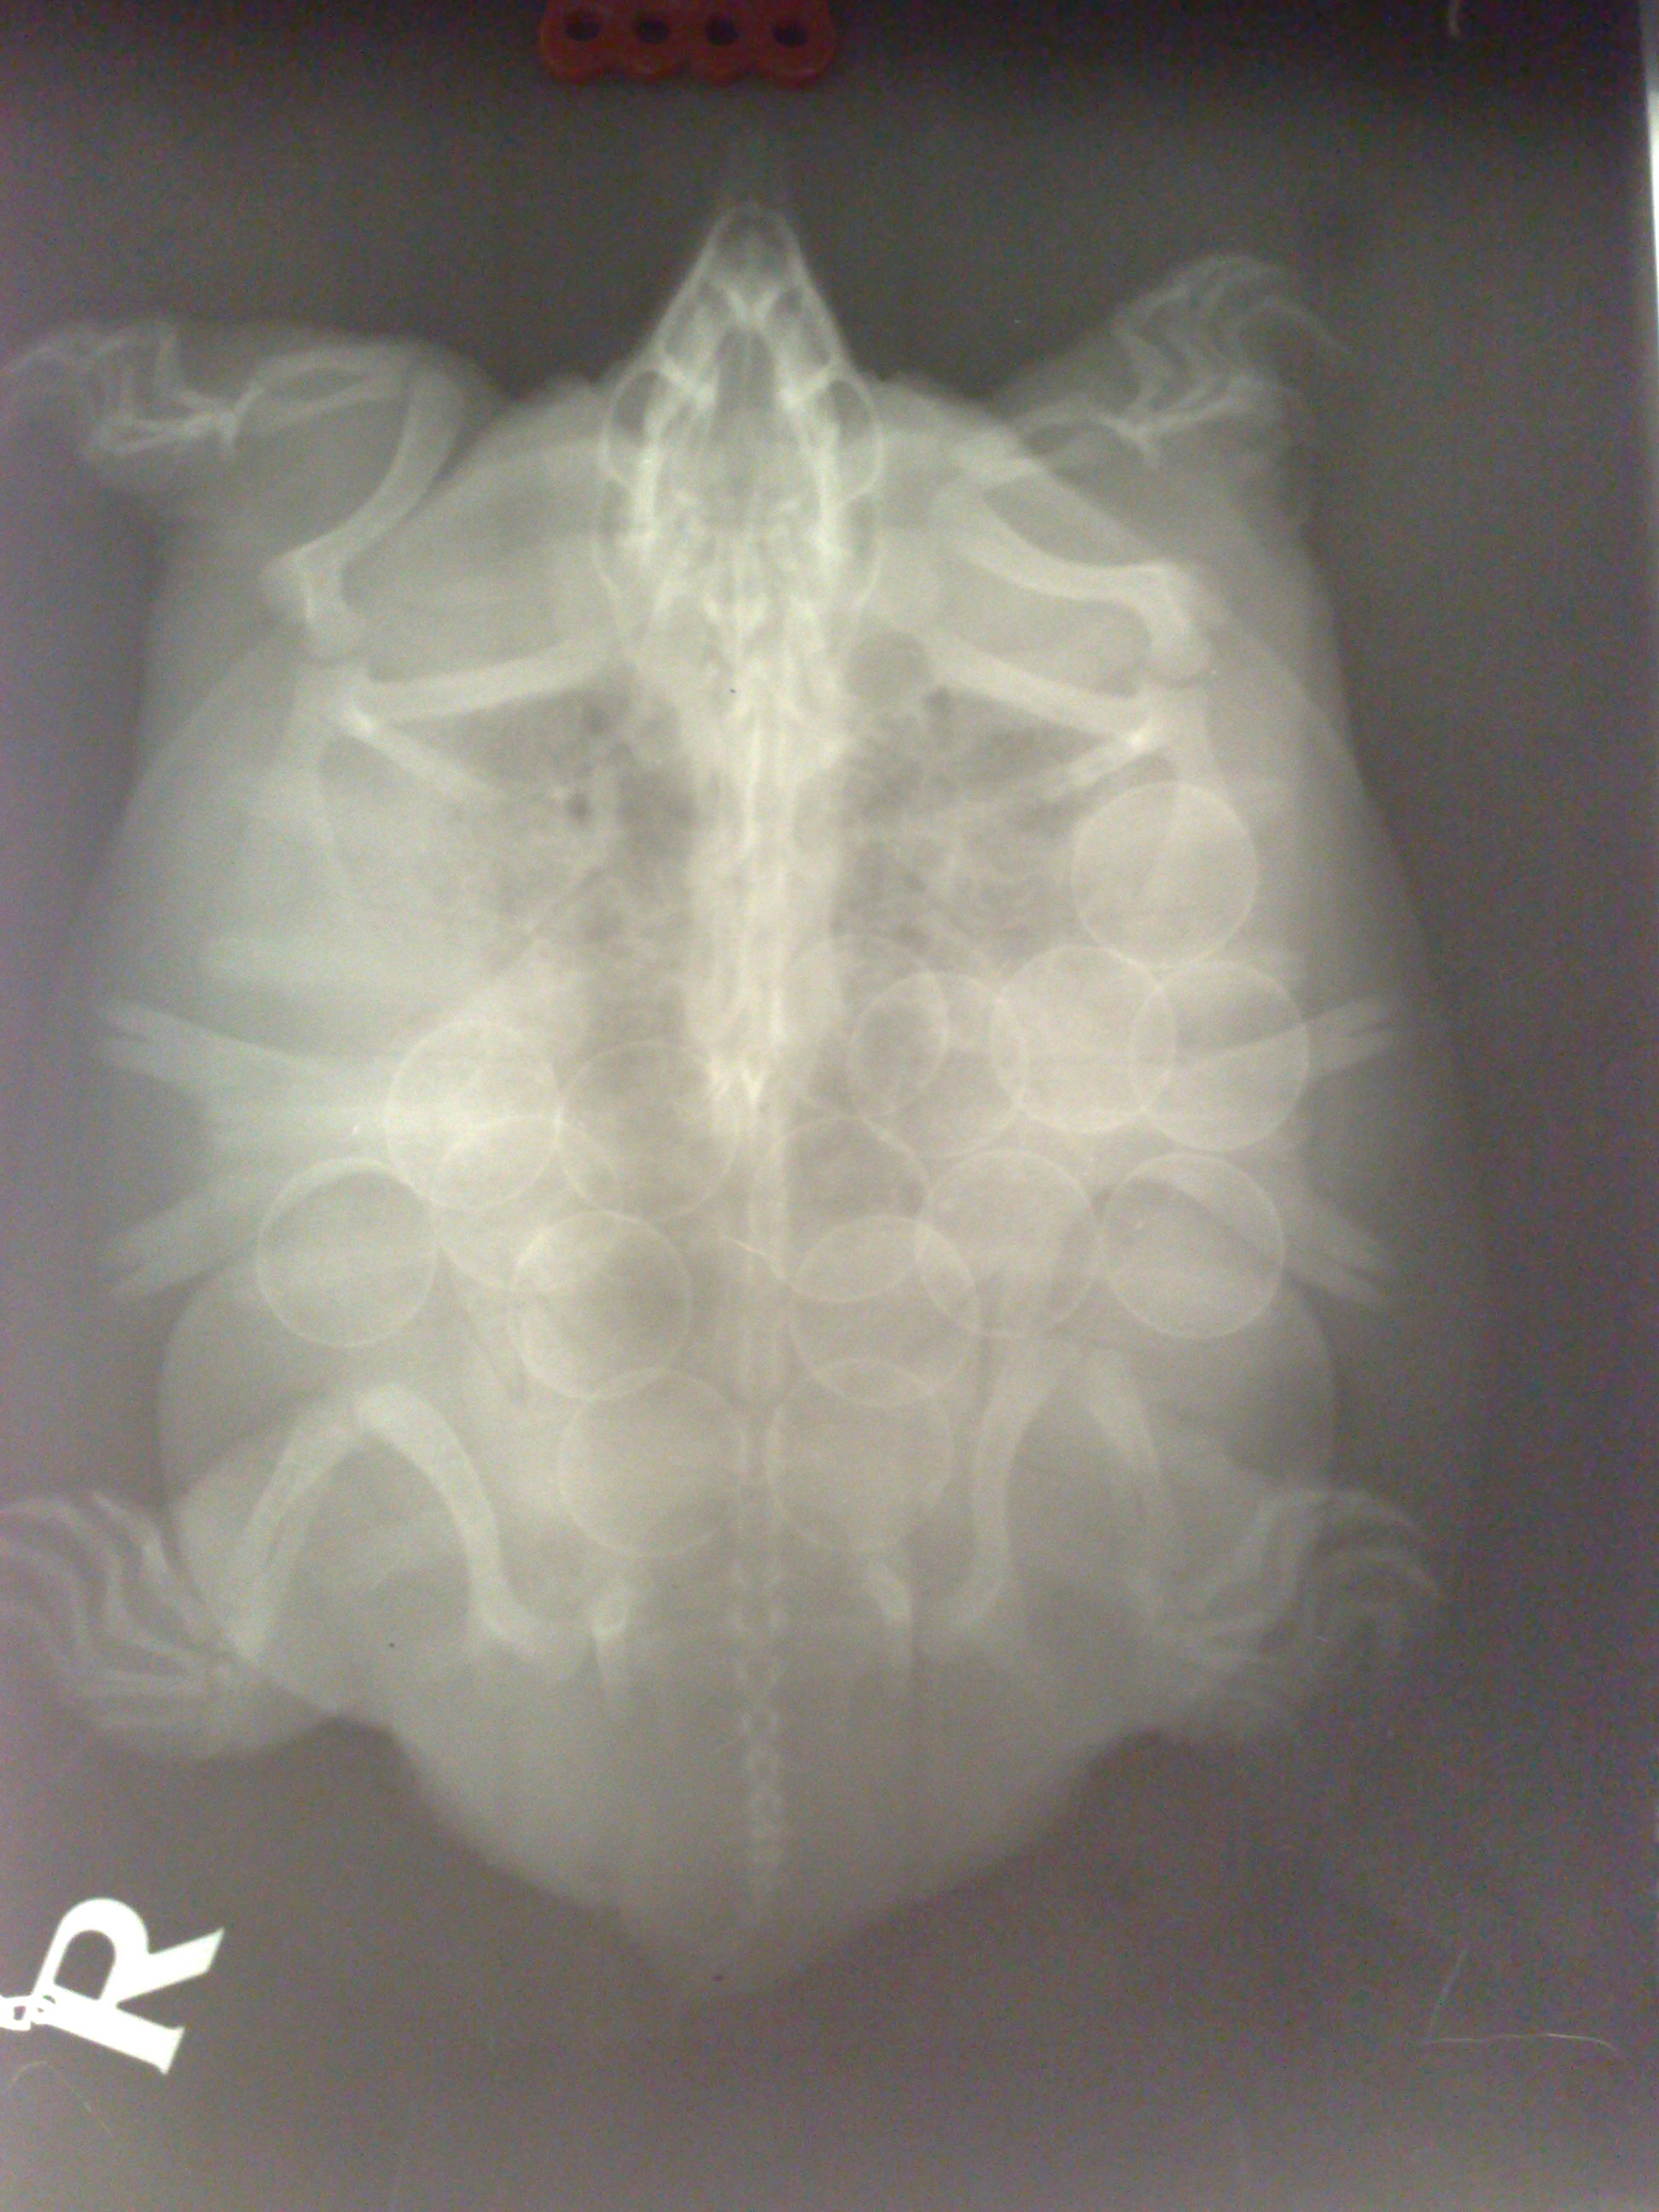

Dobrý večer, tak nakonec jsme u veterináře nedopadli nejhůře - vzhledem k malátným pohybům a apatii jsem se obávala plicního onemocnění, ale plíce jsou podle RTG čisté, jen na spodní část nebylo vidět, protože "čekáme" dalších 16 vajec :)proto omezen příjem potravy a pomalejší reakce, protože želva je doslova "plná vajíček". Ubrali jsme vodu, tetry jsem přesunula k samci a z "patra", které se nachází v levé části AT jsme udělali souš s nakloněnou rovinou písku, aby byl přítup jednodušší. Tak snad už bude vše v pořádku...

Tak máme vejce

RTG ukazoval, že jich bude 16 a máme jich 16. Chtěla bych se zeptat, jestli je vhodné udělat ještě kontrolní RTG nebo to není nutné? Zároveň bych se chtěla zeptat, jestli již mohu AT vrátit do "normálního stavu", nebo mám ještě počkat? Jestli je třeba možné (což předpokládám, že je), že by všechna vejce nemusela být na RTG snímku vidět a mohla by třeba ještě nějaká v sobě mít? Všech těchto 16 bylo v jednom hnízdě a snesená byla pravděpodobně brzo ráno 13.8. Děkuji

Ještě přikládám foto původního RTG (až do dneška jsem ho neměla k dispozici).